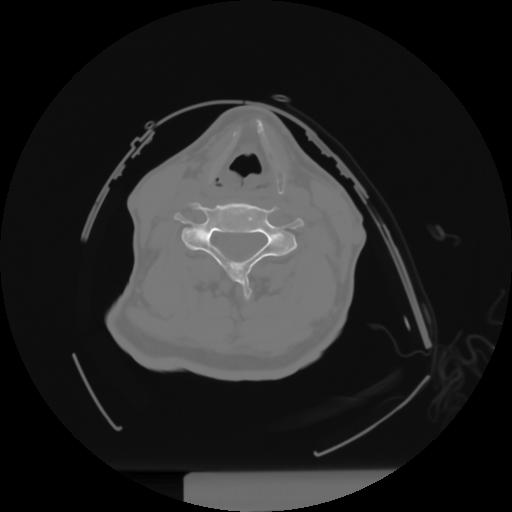

10 P.BLANDAS,,Axial,2.0,P.BLANDAS,,